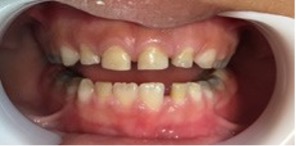

Luego de un año y dos meses, el paciente volvió al consultorio para control. Los dientes presentaban una coloración mucho más clara, principalmente, los incisivos superiores e inferiores. Pudimos observar también en la superficie oclusal de los molares inferiores un área de completa despigmentación (Figuras 4 y 5).

Figura 4: Control- 1 año. Imagen vestibular de los dientes. Se observa pigmentación verde más clara en los incisivos superiores e inferiores.

(A) Frontal y (B) Lateral izquierda

Figura 5: Control 1 año. Imagen oclusal de los dientes. (A) Oclusal inferior y (B) Oclusal superior. Se observa pigmentación verde. Pigmentación más clara en los molares y caninos superiores e inferiores